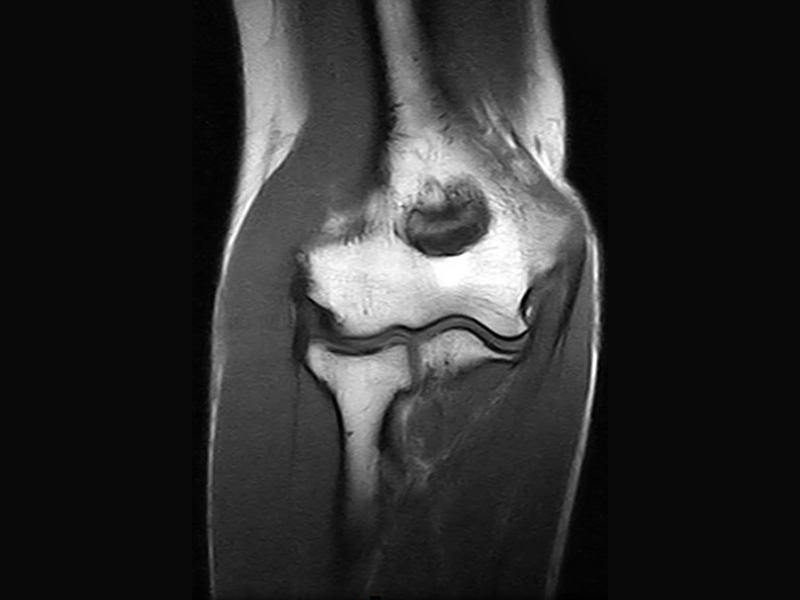

Pooperační zobrazování

Pacienti s kovovými implantáty tvoří stále větší část populace MRI. Magnifico MRI je optimální řešení, protože systém má přirozeně nízkou úroveň citlivosti na kovy ve srovnání s tradiční MRI.

Společně s vyhrazenými MAR sekvencemi nabízí Magnifico vysoce kvalitní diagnostiku také v přítomnosti většiny implantátů

Klinické snímky